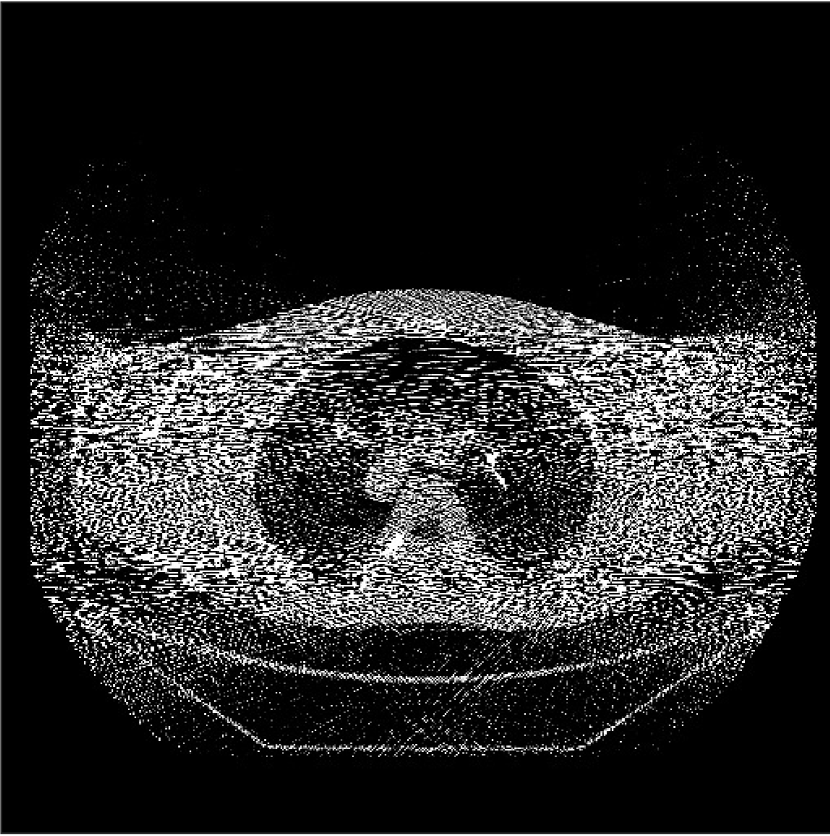

We obtained from GE a 2D fan-beam raw (pre-log) scan of a shoulder phantom, which included the beam-hardening effect. The provided 200mA200mA200~{}\text{mA} with 1 second scan can be viewed as a standard-dose scan and all the raw measurements are positive. Based on this standard-dose scan, we simulated an ultra low-dose scan as shown in (15) with α=200𝛼200\alpha=200, and added Poisson and Gaussian noise (σ=5𝜎5\sigma=5) to the measurements. The simulated measurements have about 0.4%percent0.40.4\% non-positive values. The sinograms were of size 888×984888984{888\times 984}, and reconstructed images were of size 512×512512512{512\times 512} with Δx=Δy=0.9766subscriptΔ𝑥subscriptΔ𝑦0.9766{\Delta_{x}=\Delta_{y}=0.9766} mm.

Refer to caption

Figure 10: Reconstructions for ultra low-dose 2D scan simulated from raw measurements. The leftmost image is the PWLS-EP reconstructed image for the 200 mA200 mA200\text{ mA} scan. The second image is the PWLS-EP reconstruction for the simulated ultra low-dose scan, and it is the initial image for WavResNet [46], PWLS-ULTRA [38], and SPULTRA. The display windows are [800, 1400] HU.

V-C2 Results

Fig. 10 shows the reconstructions for the 200 mA200 mA200\text{ mA} scan (reference image) along with the reconstructions for the simulated ultra low-dose scan obtained with PWLS-EP, WavResNet, PWLS-ULTRA, and SPULTRA. Visually, WavResNet fails to reconstruct the image but improves over the initial PWLS-EP reconstruction, while PWLS-ULTRA and SPULTRA provide better image quality. This indicates that the ULTRA-based methods may have a better generalization property than WavResNet, since they learn more fundamental features of CT images (also see [38]). We selected three smooth ROIs, where the pixel values are approximately constant. Tab. V(b) shows the mean and the standard deviation of pixel values for these ROIs for various methods and the standard-dose reference. Since the iterative RNN version of WavResNet only has small improvements over PWLS-EP, the pixel values do not change much compared with PWLS-EP. PWLS-ULTRA however reduces the bias in the central region of the image (ROI 2), but fails to correct the bias in the regions near the bones (ROI 1 and ROI 3). SPULTRA reduces the bias in the central region of the image, and also significantly corrects the bias near the bone regions. The standard deviations of the ROIs reconstructed by SPULTRA are comparable to those reconstructed by PWLS-ULTRA, and are close to those of the reference ROIs. Additionally, SPULTRA reconstructs the bone (indicated by the magenta arrow in the last two subfigures of Fig. 10) better than PWLS-ULTRA.